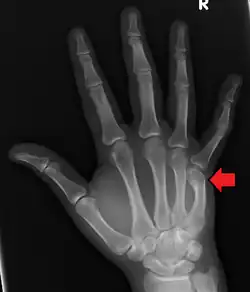

| Boxer's fracture of the 5th metacarpal head from punching a wall | |

A boxer's fracture is the break of the fifth metacarpal bone of the hand near the knuckle.[4] Occasionally, it is used to refer to fractures of the fourth metacarpal as well.[1] Symptoms include pain and a depressed knuckle.[2]

Classically, it occurs after a person hits an object with a closed fist.[3] The knuckle is then bent towards the palm of the hand.[3] Diagnosis is generally suspected based on symptoms and confirmed with X-rays.[3]